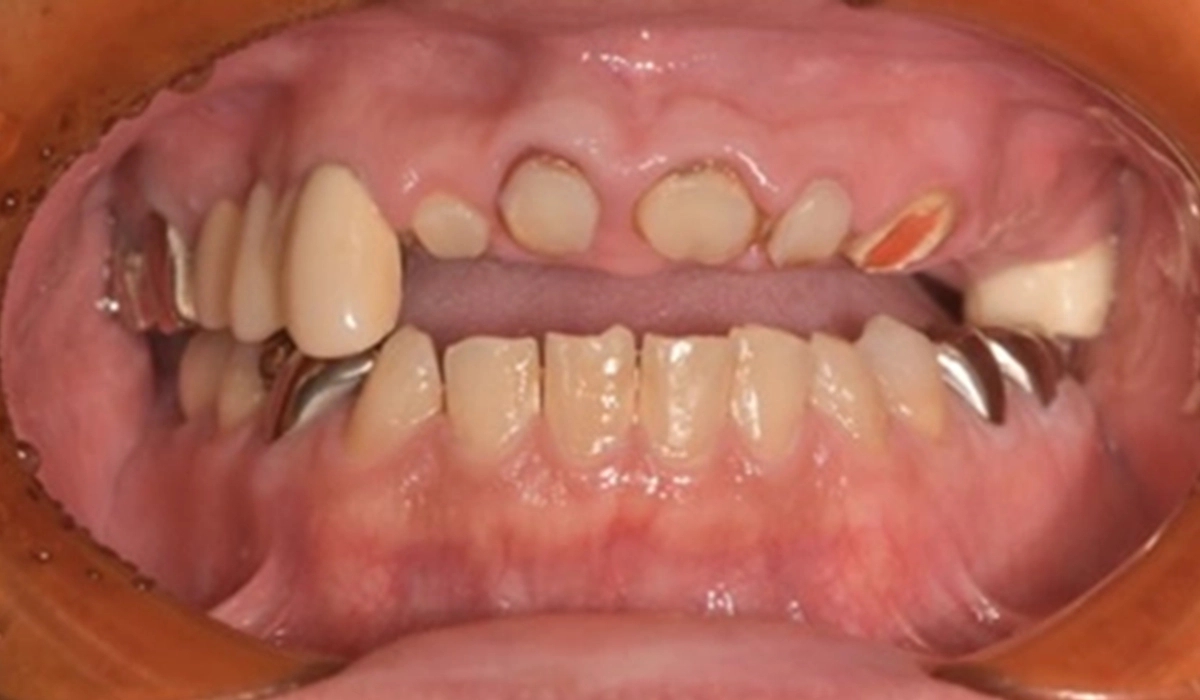

| 主訴 | 歯がぐらぐらしている |

|---|---|

| 診断 | 全体的な重度歯周炎による動揺 |

| 治療方針 | ご主人もインプラント治療で通われているため、インプラントによる治療を希望された。しかし、残せる歯は残したい思いが強かったため、将来を見据えた最小限のインプラントによる治療方針とした。 |

| 期間 | 9ヶ月 |

| 費用 | 2,716,000円 |

| メーカー | ストローマン |

| 治療後のリスク | 術後に痛みが出ることがある・術後に腫れることがある・かぶせものが割れたり、外れたりする可能性がある |